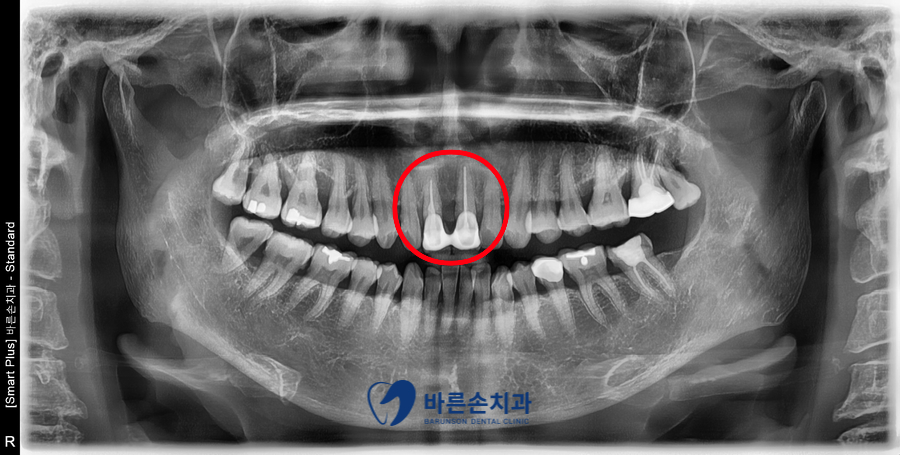

가장 가운데 앞니 2개가 연결된 형태의 크라운인데요,

가운데 잇몸 부분이 떠보이고, 잇몸 경게 라인이 크라운과 정확히 맞지 않습니다.

잇몸이 까맣게 비쳐 보이는 부분도 있네요

예전에 신경치료를 받으셨고, 보철물을 제작하였는데

시간이 많이 흘러, 잇몸이 내려간 상태 입니다.